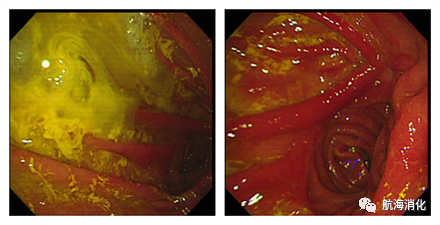

胆汁反流胃炎食管炎的症状表现不一、轻重不一、无规律性、反复发作。当出现反胃、反酸、反苦水、呕出的胃液呈黄绿色等症状时,说明有胆汁反流现象。胃镜检查时常可见胃腔内的黄绿色胆汁液,只有当胃黏膜黏附有胆汁、黏膜充血、糜烂、溃疡形成损伤时,可诊断胆汁反流性胃炎;24小时连续测定胃食管内胆汁酸可确定有否胆汁反流;胆汁酸核素扫描可确定反流的严重程度。